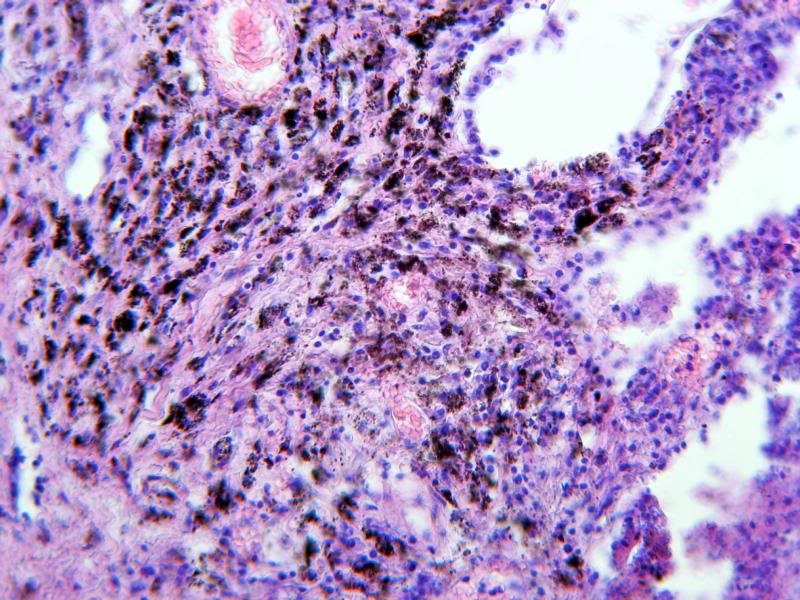

Ihr seht einen Lungenschnitt, der die Anthrakose (auch Staublunge) deutlich zeigt. Dabei handelt es sich um eine Staubinhalationskrankheit. Die vielen schwarzen Punkte sind mit kohlestäuben beladene Makrophagen. Ursache dieser Veränderung ist das häufige Einatmen von Stäuben z.B. aus Autoabgasen oder auch Zigarettenrauch. Diese Krankheit wurde erstmals bei den Arbeitern der Steinkohleminen festgestellt und erforscht.

Ich hoffe die Bilder gefallen euch. Sie sind zwar nicht ganz optimal, aber das wesentliche erkennt man. Zum Histologischen kann ich euch leider nicht mehr erzählen, dazu fehlt mir einfach das Wissen. Ich finde es aber trotzdem sehr interessant, sich diese Ablagerungen anzusehen. Die Bilder selbst wurden alle mit meiner A540 am Zeiss Standard gemacht und mit PSE 5.0 leicht nachbearbeitet.